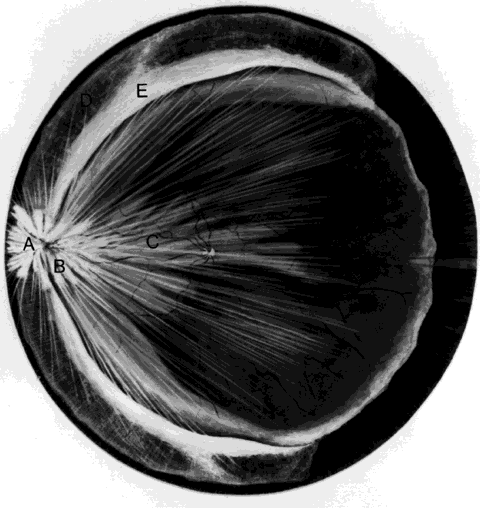

Retinal breaks are created at the time of nonpenetrating blunt injuries3 in 10% to 20% of eyes.3–6 Retinal dialyses are most frequent2–6 and are most often found in the lower temporal (Fig. 2) and upper nasal periphery (Fig. 3).2 Large irregular breaks at the point of impact of blunt trauma are less common but are equally characteristic of nonpenetrating injuries (see Fig. 3).2,7,8 Horseshoe and opercular tears of the equatorial retina (see Fig. 3) are associated with the more characteristic breaks in 25% of eyes.2 Small round holes in atrophic retina at the point of traumatic impact and macular holes (see Fig. 3) are infrequently observed after ocular contusion.2,8

Fig. 2. Large lower temporal dialysis at the point of impact of blunt trauma. (Cox MS: Retinal breaks caused by blunt nonperforating trauma at the point of impact. Trans Am Ophthalmol Soc 78:418, 1980)